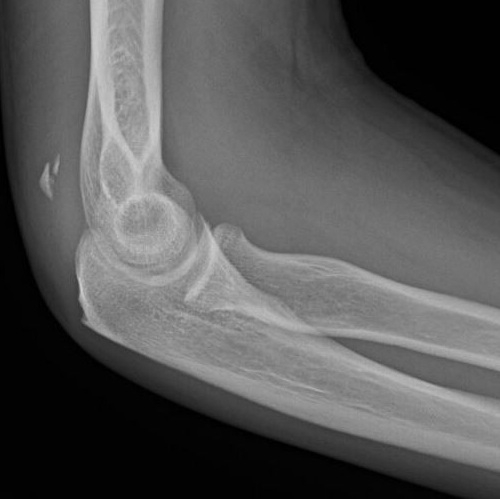

Initial Right Elbow X-Ray Impression:

1. There is a questionable occult fracture of the distal right humerus. Clinical correlation, point tenderness exam and follow up in 7-10 days is recommended if needed. No other acute fracture is noted.

Repeat Right Elbow X-Ray Impression:

1. There is stable alignment of the small ossific fragments along the posterior lower aspect of the forearm which could represent a sequelae of prior triceps injury. Correlation with symptoms suggested. The remaining imaged bones are intact. Joint spaces are within normal limits. No sizable elbow joint effusion. There is a tiny olecranon spur. Case Photo #1